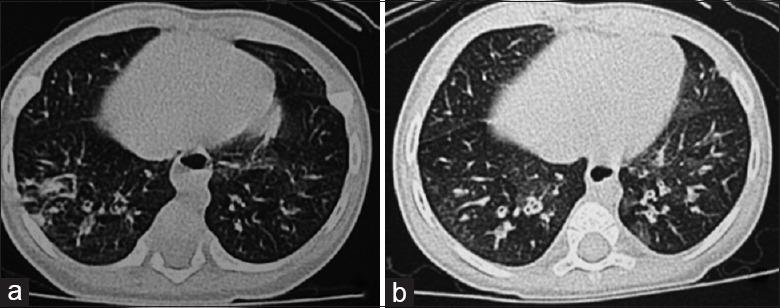

Pseudo-Bartter Syndrome in a Chinese Infant with Cystic Fibrosis Caused by c.532G>A Mutation in .

Chin Med J (Engl). 2017 Nov 20;130(22):2771-2772. doi: 10.4103/0366-6999.218015.

https://cdn.ncbi.nlm.nih.gov/pmc/blobs/45a1/5695073/f018caed8b01/CMJ-130-2771-g001.jpg